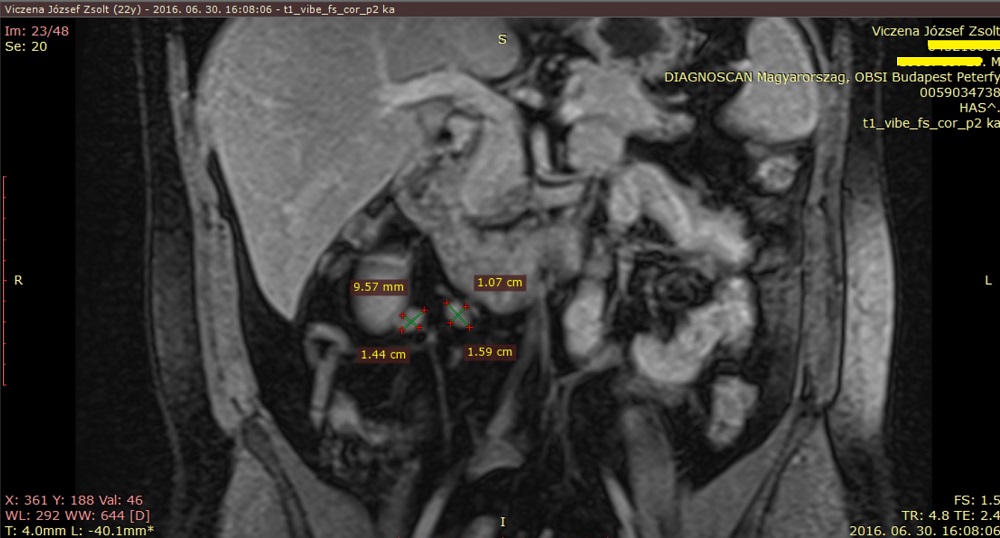

2016-ban, két évvel a betegség kezdete után továbbra is kimutatták egy újabb kontrasztanyagos teljes has-kismedence MR-en.

Zsoltnál nagyrészében mesenterialis nyirokcsomók voltak, de volt több megnagyobbodott retroperitoneális nyirokcsomó is, több mint 3,5 év után, még 2017 decemberében is az alábbi méretű és elhelyezkedésű nyirokcsomók voltak láthatók Zsolt MRI-jén. Tehát a lelet 2017-es, de 2020-ban egy újraátnézés során a radiológus pontosabban megvizsgálta és leletezte a nyirokcsomókat, többek között egy 10x21x9 mm-est is, de ezekből ismét nem történt mintavétel. (Pedig ezután az MR után történt nagy hasi műtét /laparotomia/, ahol erre minden lehetőség meg lett volna!)